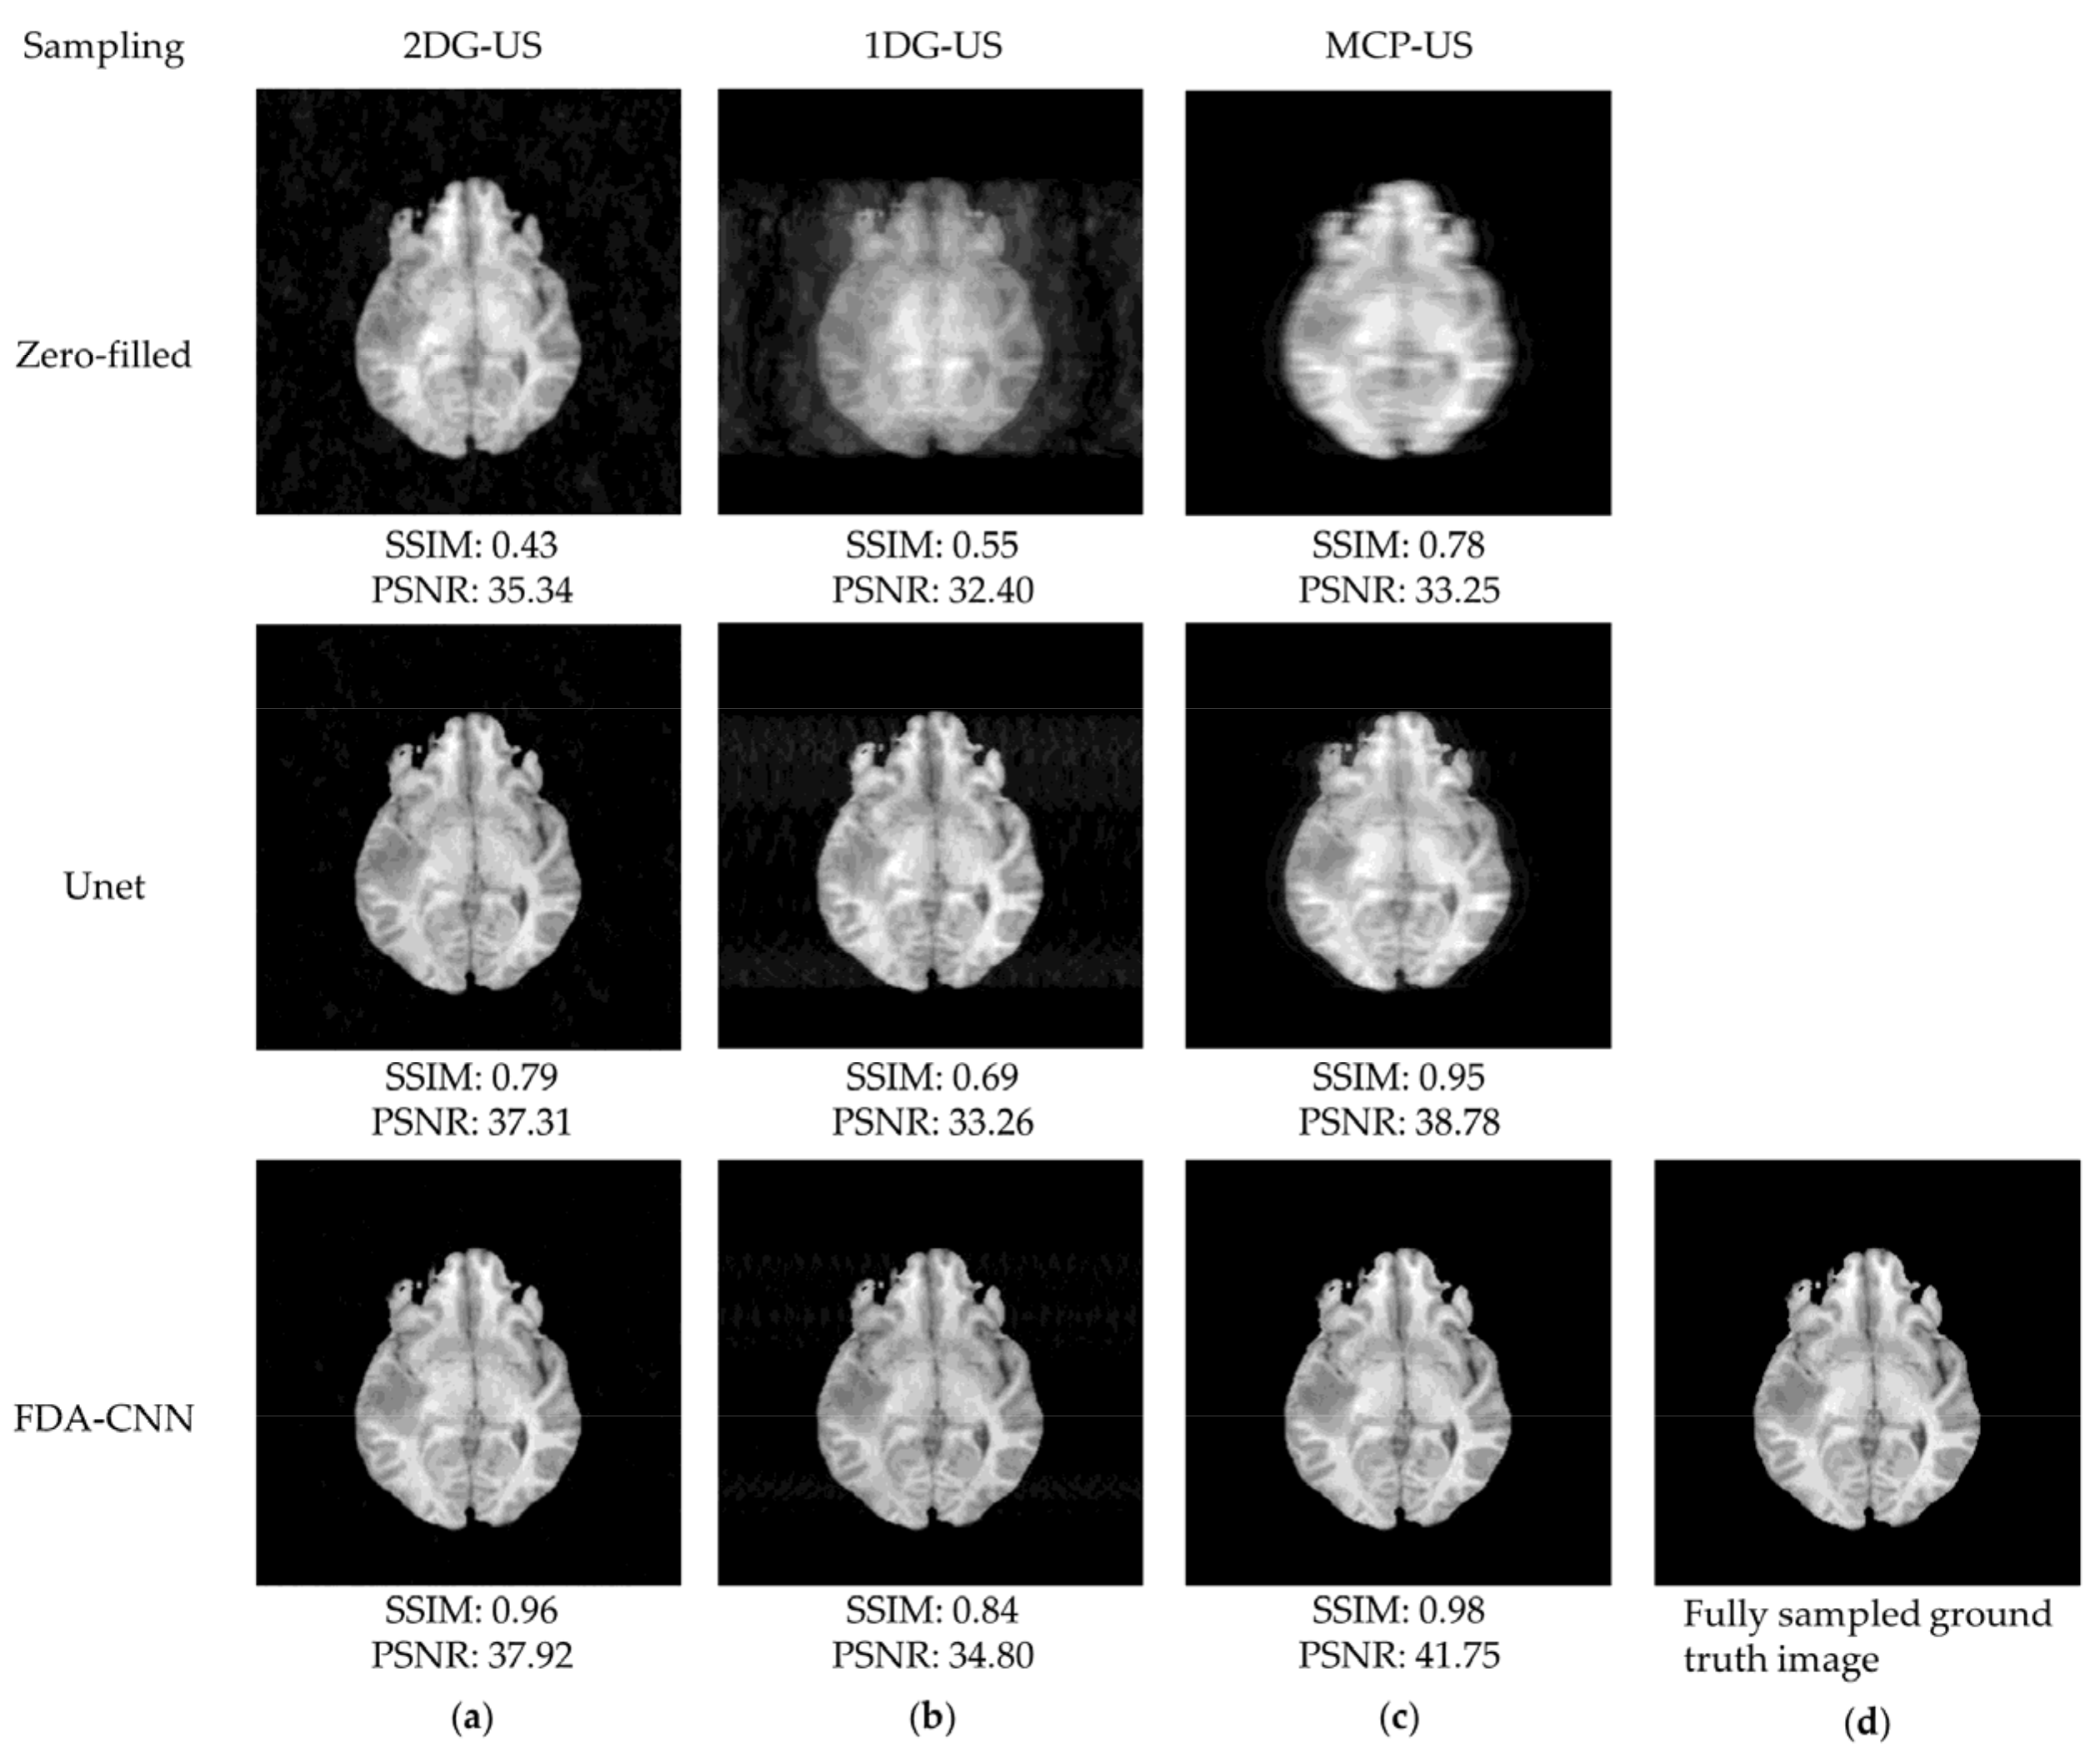

4.2. FastMRI and IXI Datasets